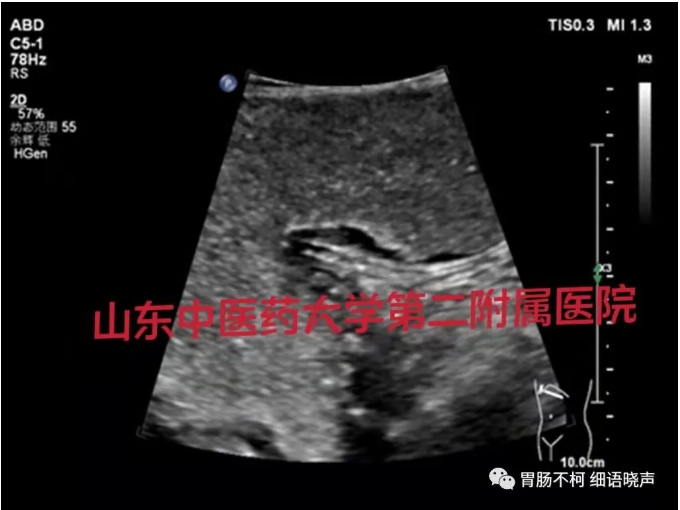

病例一,胃体前壁胃壁增厚性病变: